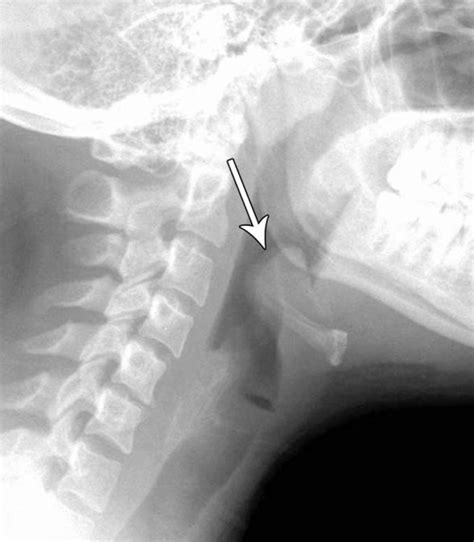

Radiological Identification: The Thumbprint Sign

The Thumbprint Sign Epiglottitis is observed on a lateral soft tissue neck X-ray. Under normal conditions, the epiglottis appears as a thin, wispy shadow. In cases of acute epiglottitis, the inflamed tissue projects posteriorly and superiorly, creating a rounded, dense, soft-tissue opacity that resembles the distal phalanx of a human thumb. Hence, it is commonly called the "thumbprint sign."

While this sign is highly specific, it is not perfectly sensitive. A clinician should never rule out epiglottitis based solely on a "normal-looking" X-ray if the clinical suspicion remains high. The following table highlights key differences in imaging findings between common airway obstructions: